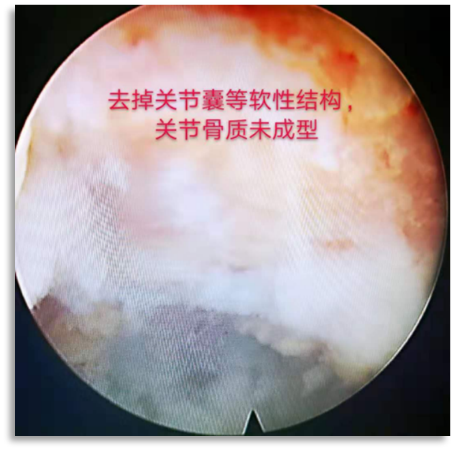

为解决以上问题���,我们提出“椎间孔镜按需成型5级法”��,即将椎间孔镜术中椎间孔成型的实际操作范围进行分级���:0级����:不成型����,见图 1��;1级���:软组织成型�����,只去除关节囊等部分软组织�����,基本不做骨性成型���,见图 2���;2级�����:少许骨质成型���,但不显露下关节突关节面����,见图 3����。3级成型�����:上关节突尖部或上1/2去除成型���,显露下关节突关节面���,见图 4�����;4级成型����:上关节突大部分成型或伴有部分椎弓����、峡部或下关节突小部分���,但预留基底部一部分��,见图 5��。

图 2 1级成型 |